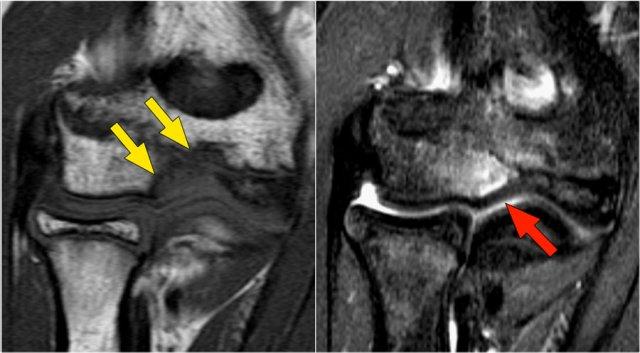

Arthrosis in valgus overload syndrome

Do quá tải valgus, có các lực cắt tác động lên phần sau-trong của khớp cánh tay-trụ.

Lưu ý tình trạng xơ cứng dưới sụn được thấy trên ảnh T1W (mũi tên đỏ).

Trên hình ảnh T2W có phù tủy xương dưới sụn và mất sụn khớp (mũi tên vàng).

Đây là hình ảnh của một vận động viên bóng chày 20 tuổi.

Trên các hình ảnh mặt phẳng coronal, bó trước của dây chằng UCL hiện rõ đẹp, nhưng lưu ý rằng có sự hình thành gai xương ở phần trong của khớp (mũi tên đỏ).

Khi chúng ta đi xa hơn về phía sau có một vùng nhỏ có tín hiệu thấp (mũi tên vàng), đây là một chỗ bong gân của một phần dây chằng bên trụ (UCL).

Khi quan sát trên lát cắt ngang (axial), chúng ta có thể nhận thấy sự hình thành gai xương khổng lồ.

Lưu ý rằng dây thần kinh trụ (mũi tên màu xanh) nằm cạnh các gai xương này và những bệnh nhân này có thể biểu hiện bệnh lý thần kinh trụ.